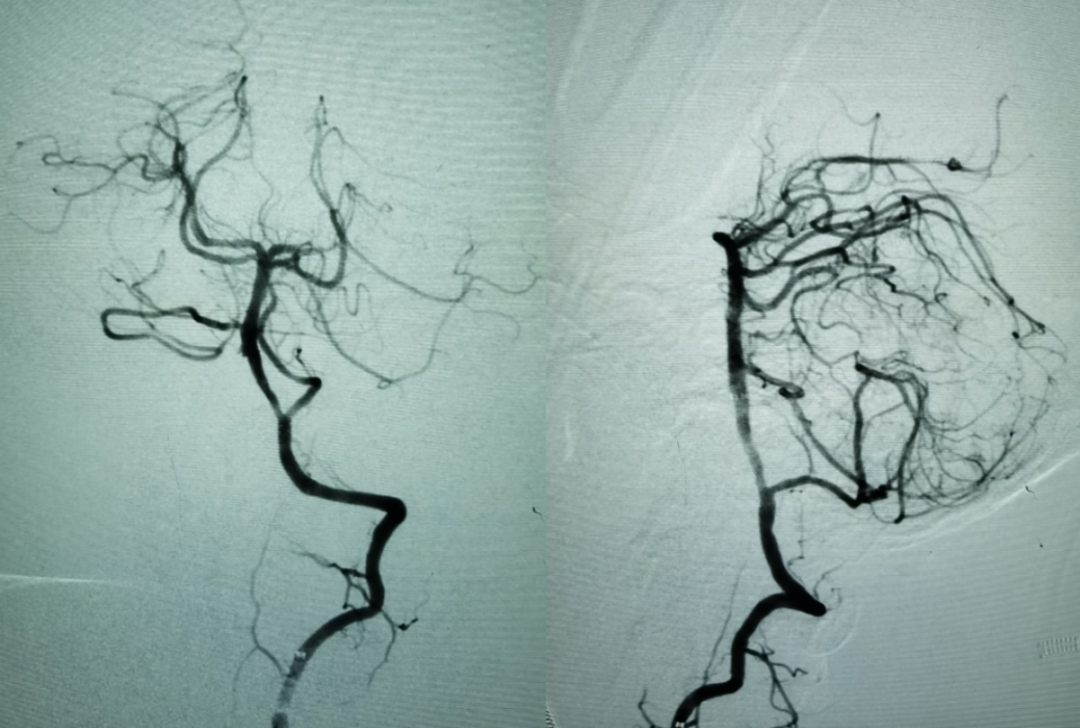

选择Neuroform EZ 3.5X20mm支架植入,术后工作角度造影如下:

术后标准正侧位。